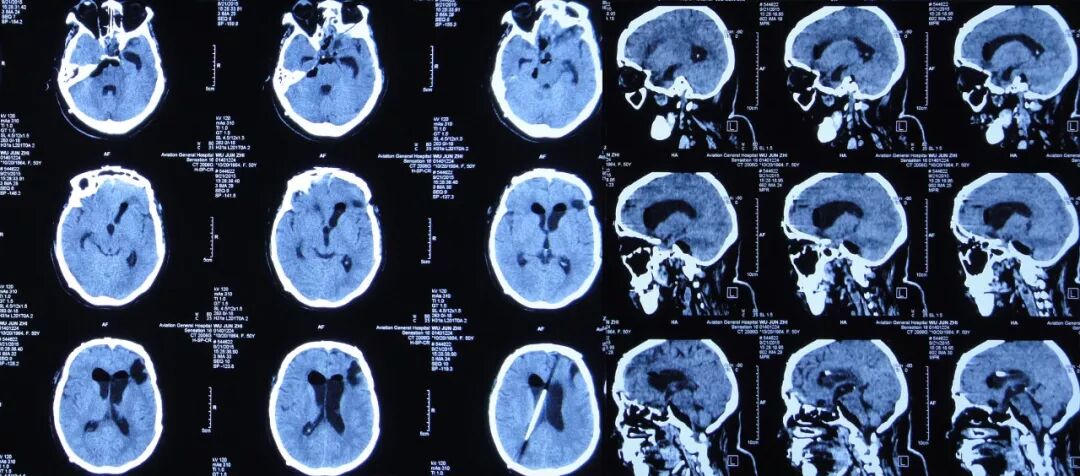

2015年8月6日,复查头CT:脑室显著扩张,室旁水肿明显,颅内积气(图15)。患者仍有脑脊液鼻漏,但当地医院不予脑脊液漏修补治疗。

图15:2015年8月6日头CT:脑室显著扩张,室旁水肿明显,颅内积气

李小勇脑脊液中心的治疗经过与结果

家属为求进一步治疗,在2015年8月7日患者急诊转来李小勇脑脊液中心。

入院后第1天即2015年8月8日,复查头CT头:脑脊液蝶窦瘘征象。脑室扩张,双侧额叶片状密度减低,左侧额叶软化灶形成;脑沟、裂变浅;鞍上池及右侧脑室前角积气(图17)。

图17:2015年8月8日头CT:脑室扩张,鞍上池及右脑室前角积气